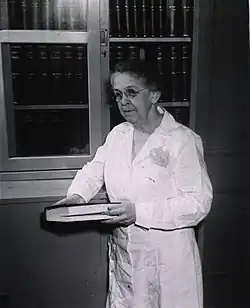

L'unification bactériologique vétérinaire et médicale est faite par la bactériologiste américaine Alice Catherine Evans (1881-1975). En 1918, elle montre que bacillus abortus de Bang (issu de la maladie bovine) est similaire au micrococcus melitensis de Bruce (issu de la maladie humaine et caprine). Ces travaux sont confirmés : la maladie humaine peut se transmettre aussi par lait de vache, et la maladie des chèvres au gros bétail[4].